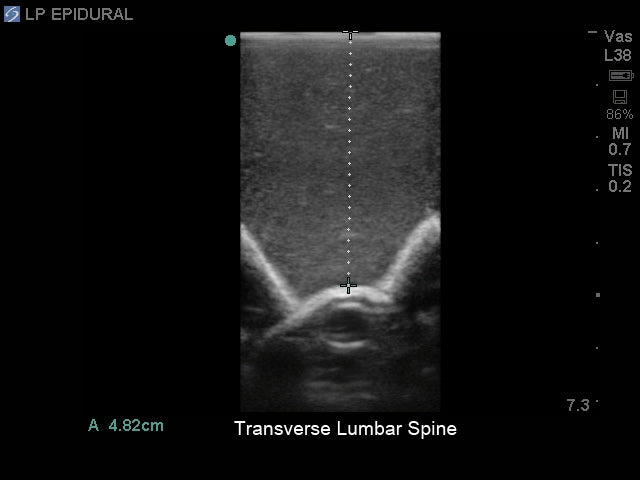

- Ultrasound can be used to identify the optimal insertion points, the angle of needle insertion, and determine the depth to the ligamentum flavum, epidural space, and spine

- Excellent ultrasound imaging properties

- Use any ultrasound system and never have to adjust system settings unrealistically or have trouble imaging the model's anatomy

- Ultra-durable self-healing tissue is extremely realistic in ultrasound imaging properties and feels like real human tissue